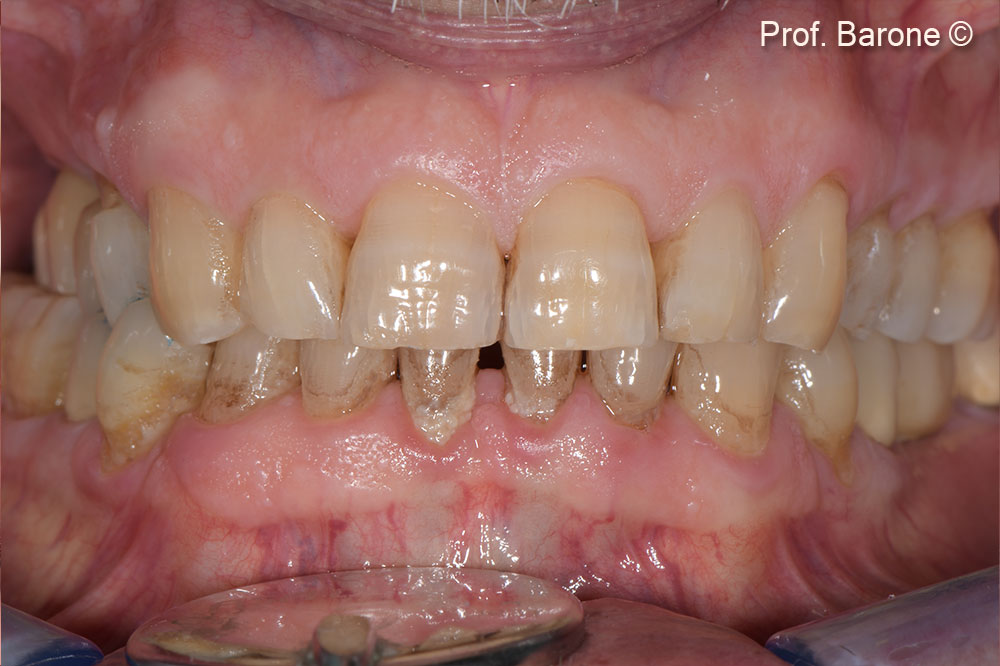

Initial situation

In a male patient (71 years old), the residual ridge height doesn’t allow implant placement.

Partial edentulism first quadrant